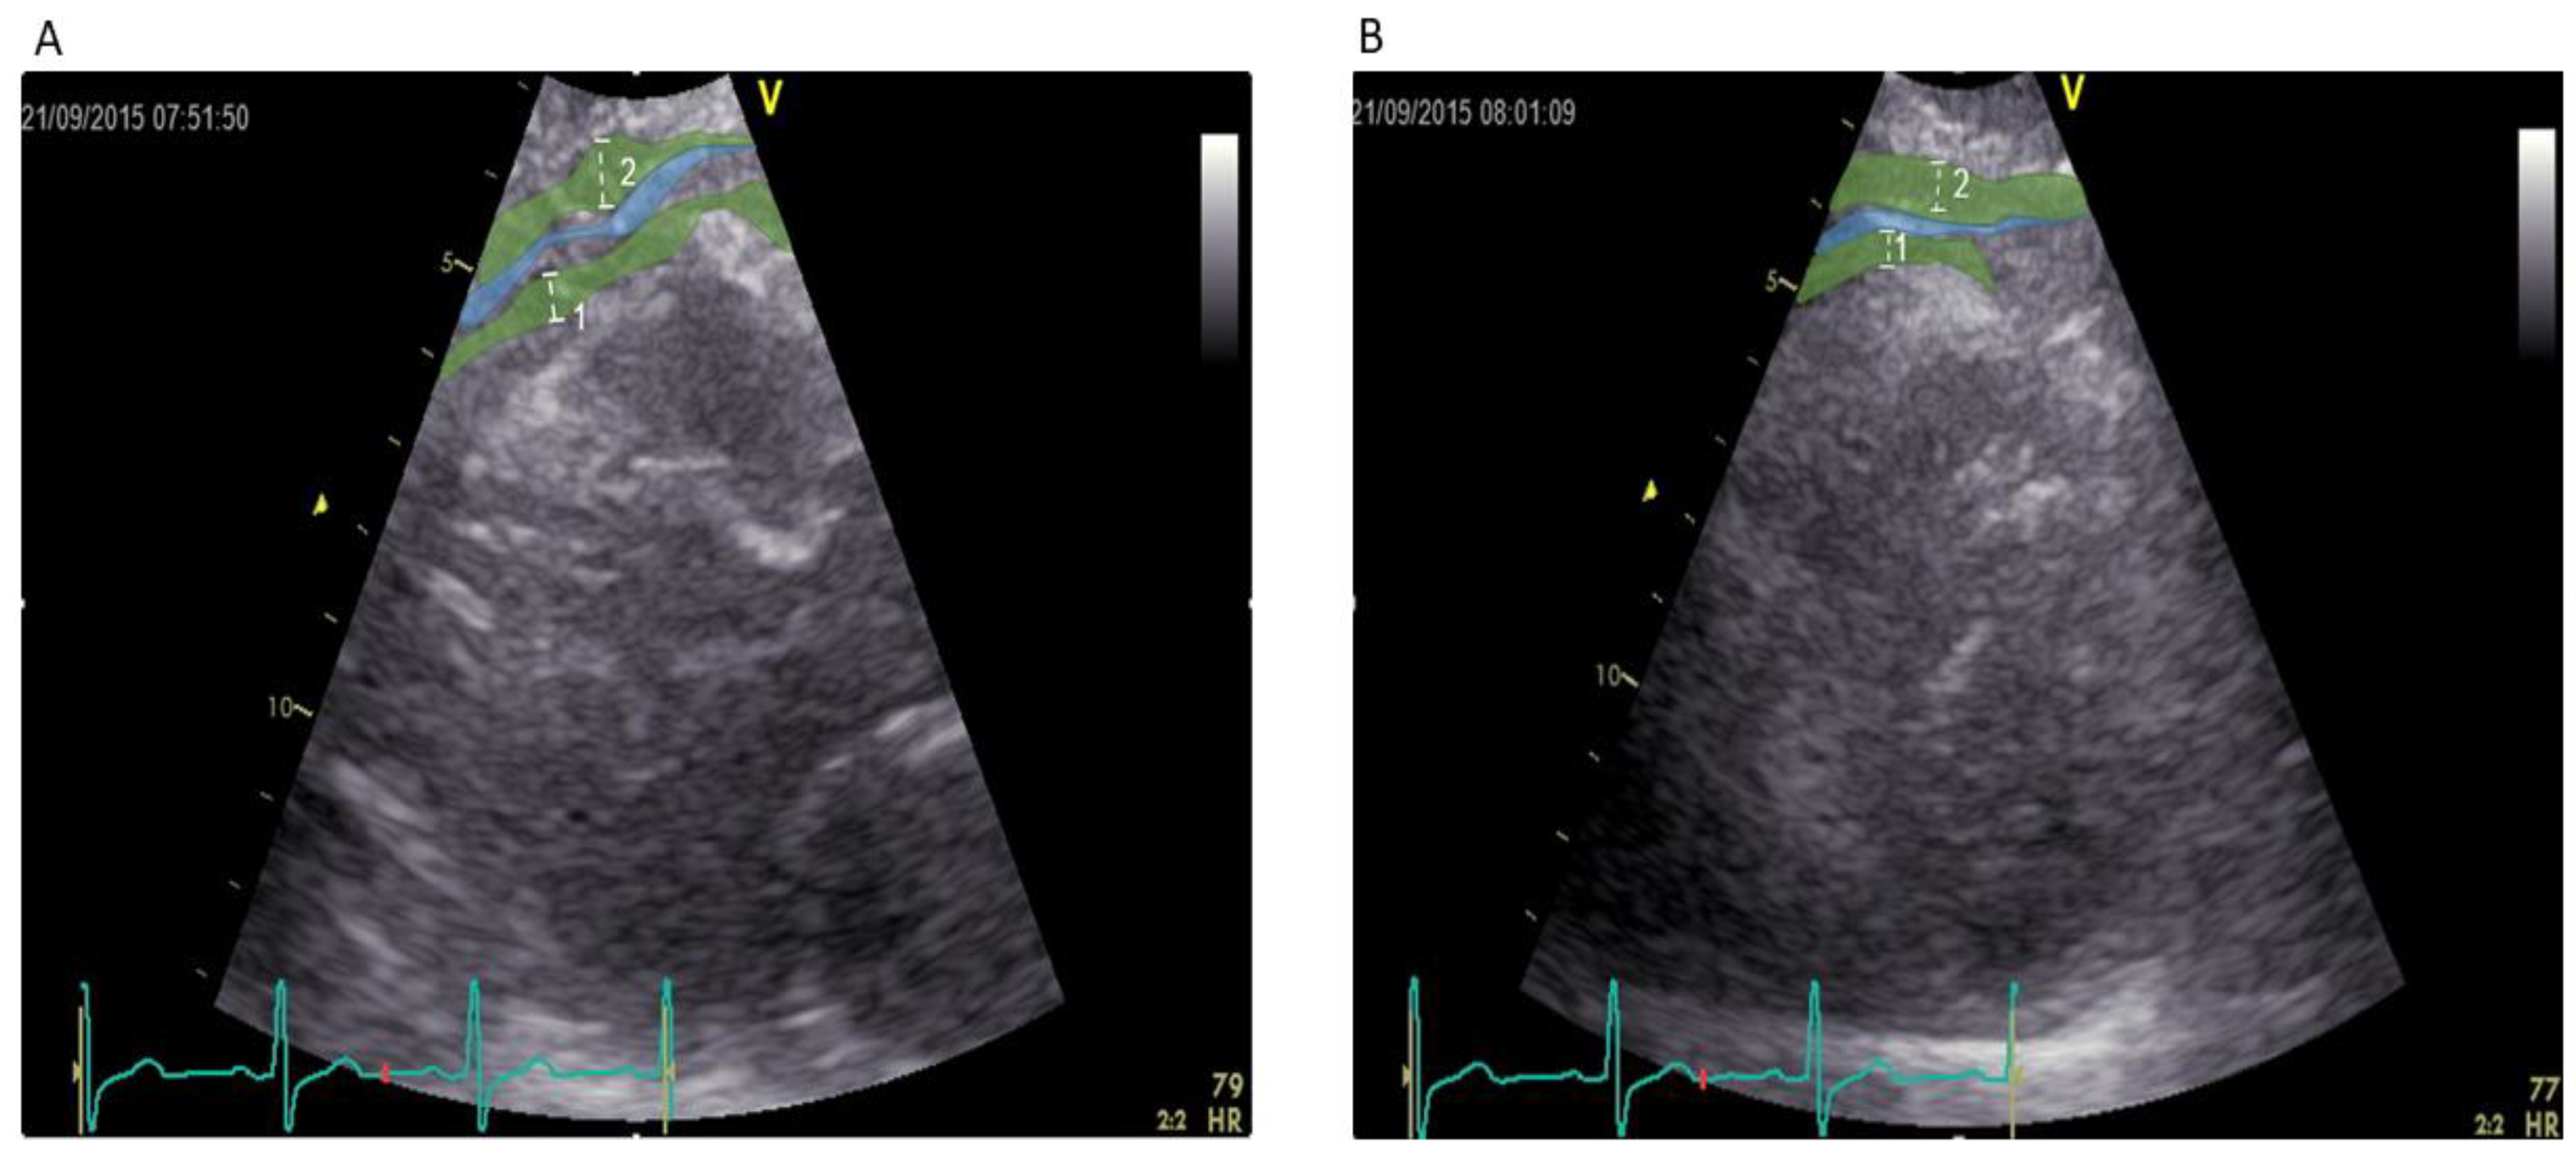

2.5. Echocardiographic Measurement of Epicardial Fat Thickness

- Iacobellis, G.; Assael, F.; Ribaudo, M.C.; Zappaterreno, A.; Alessi, G.; Di Mario, U.; Leonetti, F. Epicardial fat from echocardiography: A new method for visceral adipose tissue prediction. Obes. Res. 2003, 11, 304–310. [Google Scholar] [CrossRef] [PubMed]

- Iacobellis, G.; Willens, H.J. Echocardiographic epicardial fat: A review of research and clinical applications. J. Am. Soc. Echocardiogr. Off. Publ. Am. Soc. Echocardiogr. 2009, 22, 1311–1319. [Google Scholar] [CrossRef] [PubMed]